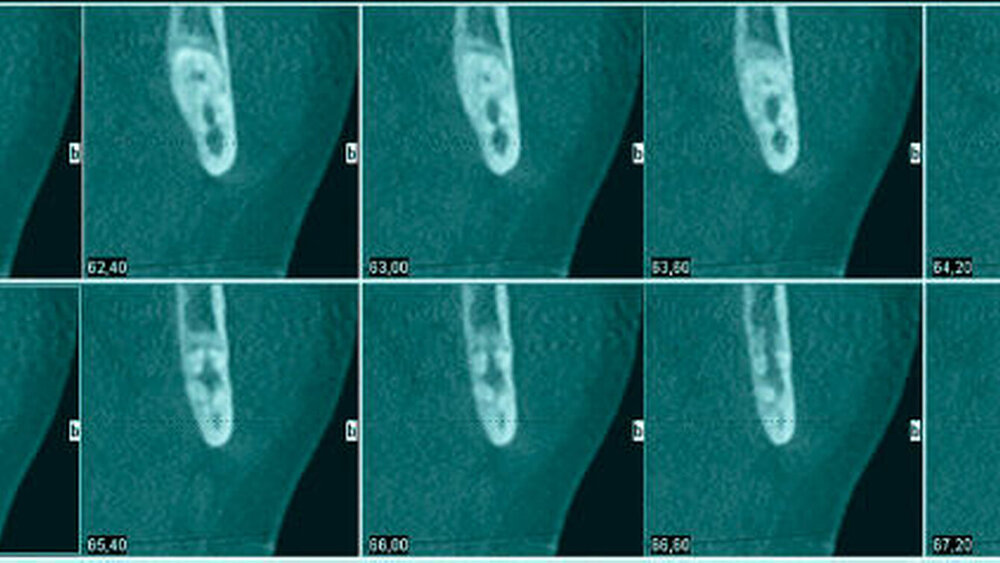

Aufgrund der engen Lagebeziehung der Weisheitszähne zum Nervus alveolaris der jeweiligen Seite wurde zur weiterführenden Diagnostik eine digitale Volumentomografie durchgeführt.

In der 3-D-Aufnahme bestätigte sich der Verdacht, dass der Nerv zwischen den Wurzeln hindurch zog, wobei beim Zahn 48 die Wurzeln den Nerv komplett umklammerten (Abbildungen 3 und 4). Nach Inzision auf dem aufsteigenden Unterkieferast mit Entlastung an den Zähnen 37 beziehungsweise 47 wurden der Knochen und im Weiteren die Weisheitszähne dargestellt. Die Kronen wurden von der Wurzel getrennt, die Wurzeln separiert und sukzessive entfernt, wobei die Integrität der Nerven auf beiden Seiten erhalten blieb (Abbildung 5).

Eine Verletzung des Nervus alveolaris inferior bei Weisheitszahnentfernung findet sich überproportional häufig in Fällen, in denen auf der Panoramaschichtaufnahme Zeichen zu erkennen sind, wie eine Veränderung des Verlaufes des Nervus alveolaris inferior (Abbildungen 1 und 2), bei überlagerungsbedingter erhöhter Transluzenz im Bereich der Überprojektion von Wurzel und Nerv und bei Unterbrechung der kortikalen Begrenzung des Nervkanals [Blaeser et al., 2003]. Alle diese Kriterien lagen im vorliegenden Fall vor. In der weiterführenden digitalen Volumentomografie ist zu erkennen, wie der Nerv zwischen den Wurzeln liegend hindurchzieht.

Man kann den Nerv-Verlauf im DVT besser beurteilen als in der Panoramaschichtaufnahme.